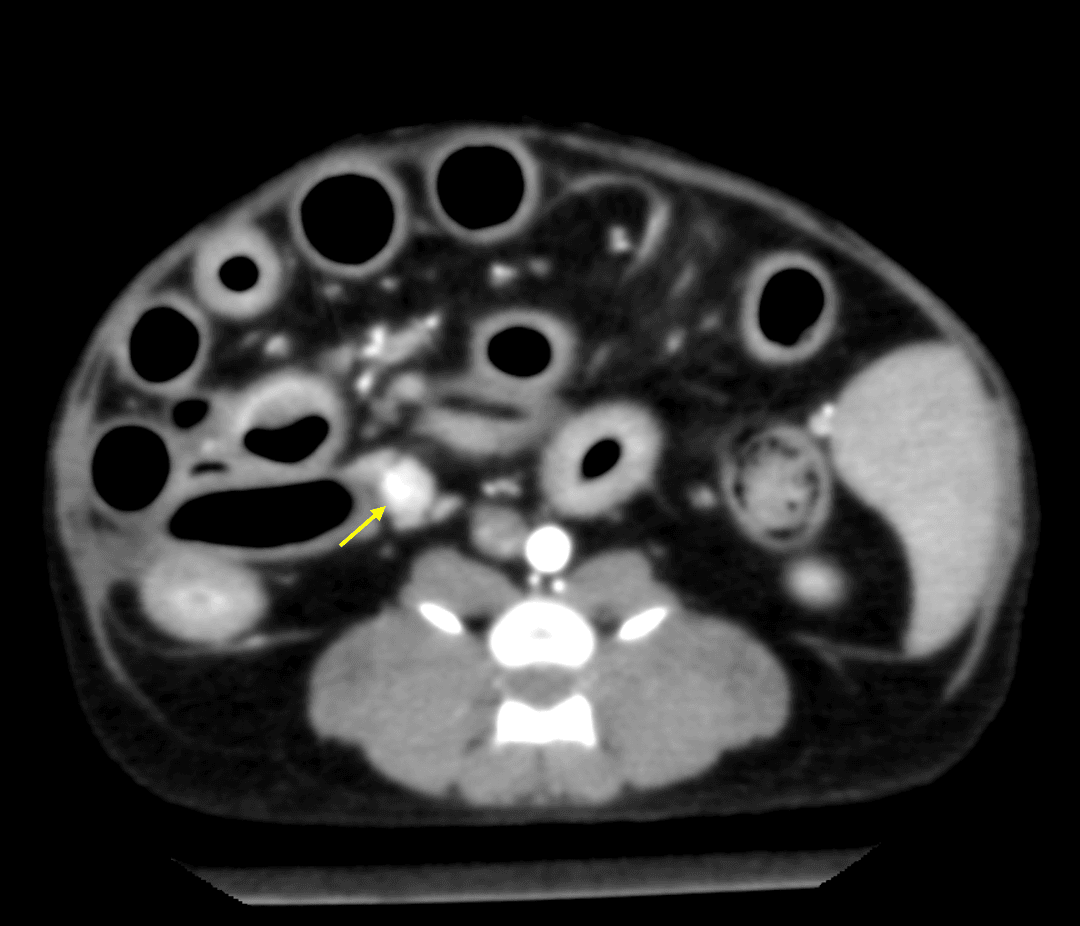

リンパ腫、乳腺腫瘍、肥満細胞腫などの腫瘍性疾患から、腎不全、尿路結石、膀胱炎、前立腺疾患などの腎泌尿器疾患まで、専門的な知見に基づいた診断と治療をご提供します。大切なご家族の病気に専門医が寄り添い、最適な治療をご提案できるよう努めてまいります。

腫瘍科外来

犬・猫のリンパ腫、乳腺腫瘍、肥満細胞腫などの腫瘍性疾患の診察と治療を行います。